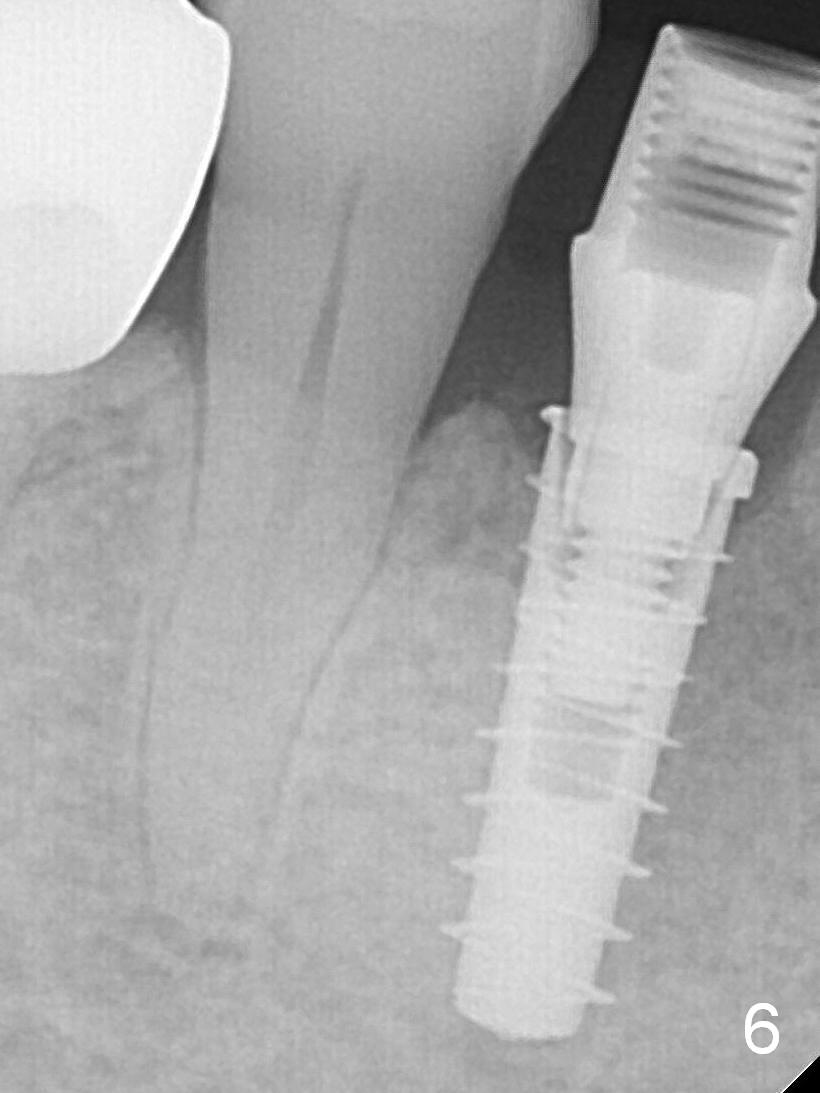

After placement of a 4x11 mm implant, a 4.5x4(2) mm abutment is inserted (Fig.4). Three months postop (Fig.6,7 (incomplete abutment seating (hand tightening))), the implant is loaded for intrusion of the opposing supraerupted tooth.